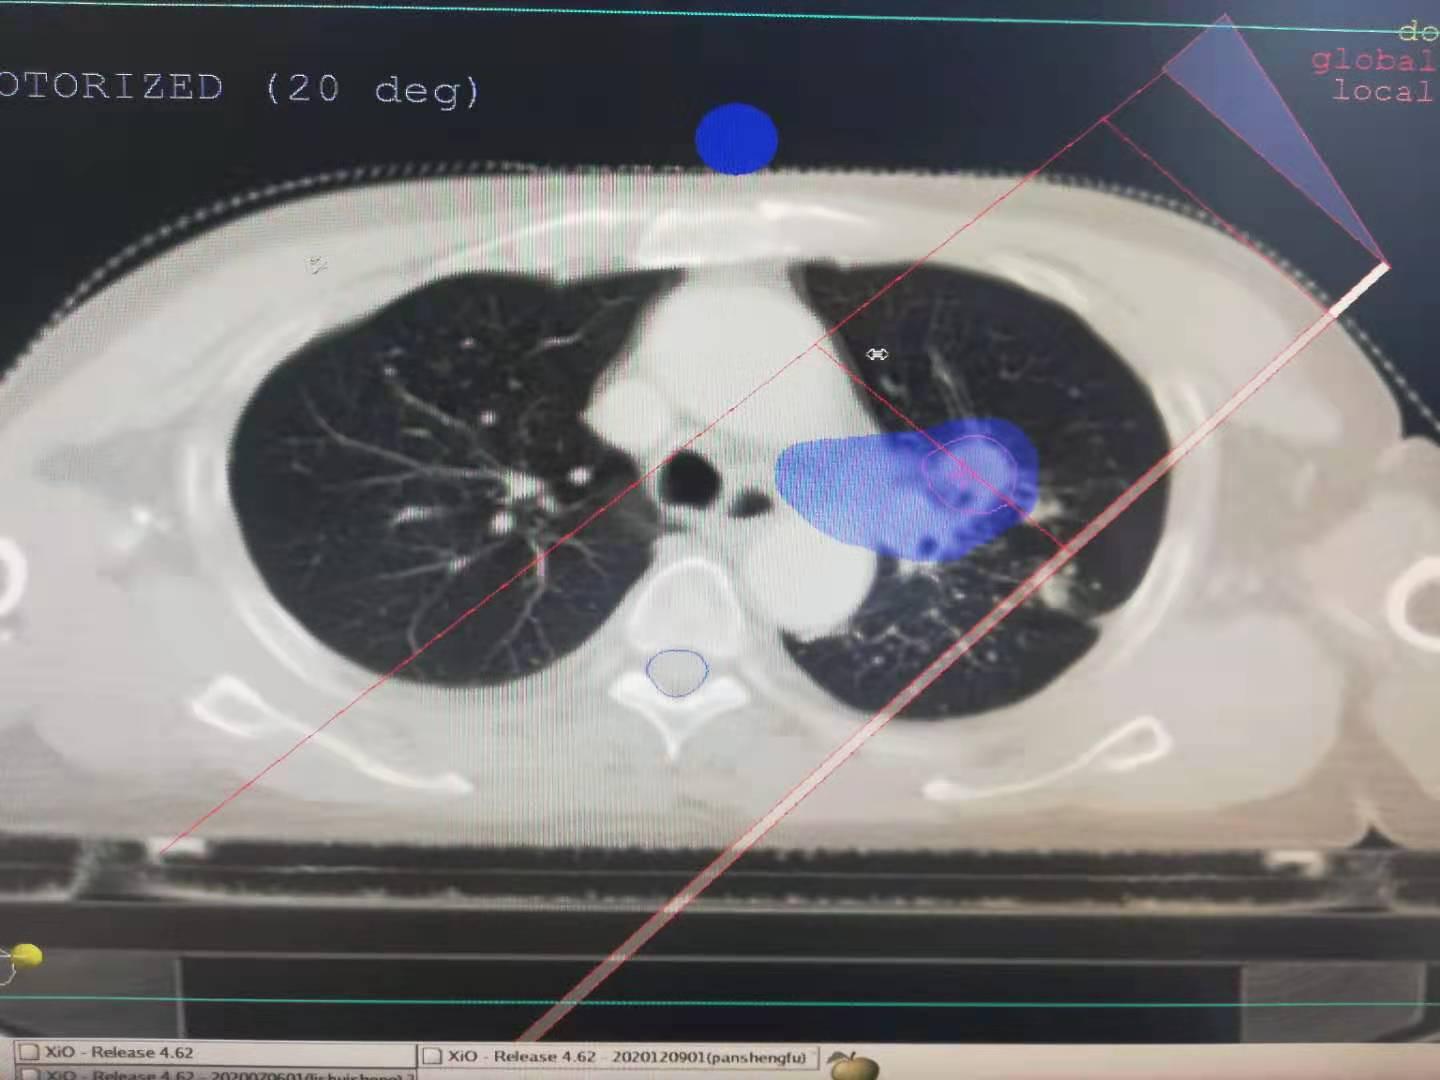

李某某今年56岁,因反复咳嗽咳痰、胸闷3月余于2020年4月来我院肿瘤科住院。胸部增强CT:“左肺中央型肺癌并左上叶阻塞性不张,纵隔淋巴结肿大”。电子支气管镜见左上叶新生物,病理及免疫组化:(左上新生物)“恶性肿瘤,符合鳞状细胞癌”。基因检测:未见热点基因突变,PD-L1阴性。予以化疗3程后,咳嗽,咳痰,胸闷等症状好转,左上肺肿瘤缩小,2取得了较好的治疗效果,2020年06月予以胸部放射治疗,治疗顺利。2020年08月提示左上肿块缩小,同时可见磨玻璃样影及小片、索条状影,与放射野相仿,考虑急性放射性肺炎。给予抗炎治疗后,左肺磨玻璃样影明显吸收。然后继续抗肿瘤治疗。

两张图片对比分析,典型的射野途径上产生的放射性肺炎,患者经抗炎治疗后好转。

放疗是局部治疗,放疗机发射放射线,汇聚在肿瘤靶区。虽然当今的放疗设备与二维放疗时代大有改进,但射线要经正常组织才能到达肿瘤,必须要经过一定的路线,会对途中的组织造成损伤,包括皮肤、食管以及正常的肺等,导致放射性损伤,并产生无菌性炎症,所以放疗有一定的风险。随科技进步越来越多的精准放疗方式应运而生,比如TOMO刀、射波刀,质子重离子等,其中碳离子放疗是目前最理想的放疗技术,但其治疗费用昂贵。